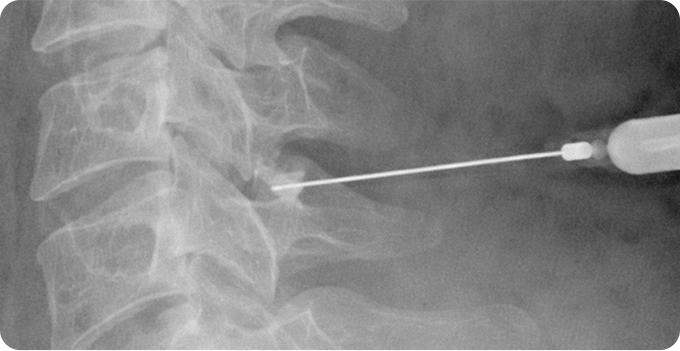

신경차단술 사진

1

신경차단술

신경에 약물을 주입해 염증과 통증을 완화하는 비수술적 치료입니다. 시술이 간단하고 비교적 안전하며, 즉각적인 통증 완화 효과를 기대할 수 있습니다. 목 디스크뿐만 아니라 척추관 협착증 등 다양한 신경통 치료에 사용됩니다. 다만, 일시적인 완화에 초점이 맞춰져 근본적인 문제 해결을 위해 추가 치료가 필요할 수 있습니다.